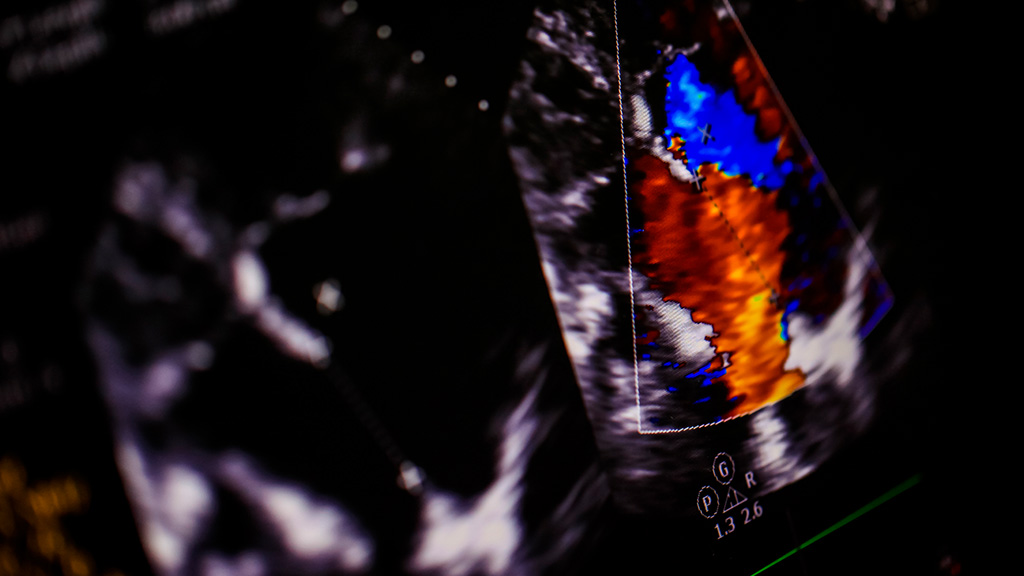

Ultrasonido Perfil Biofísico Fetal